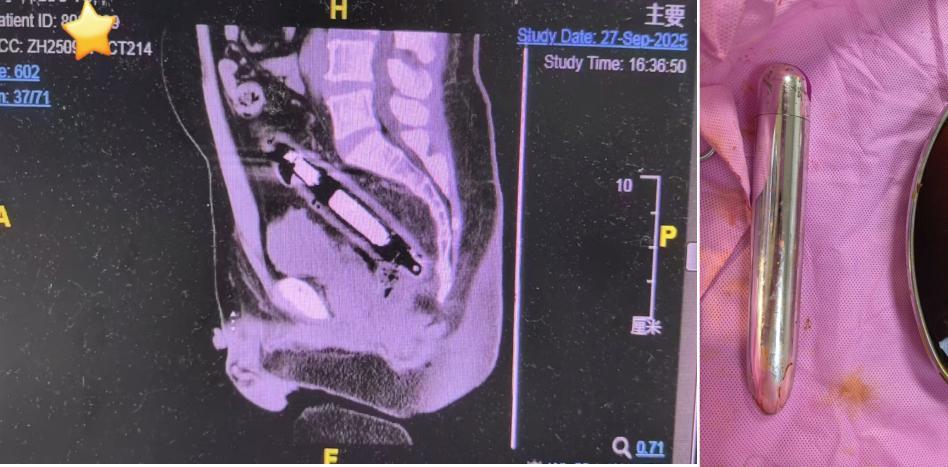

副主任医师李心茹检查确定该异物为约30厘米长的圆柱状金属物。考虑到金属物质坚硬,若不及时取出,极有可能扎破肠道引发穿孔,治疗团队当即为王先生制定紧急手术方案。在快速完善各项术前准备、麻醉成功后,手术当日顺利开展。最终,医生成功将金属异物取出,术后王先生恢复良好。